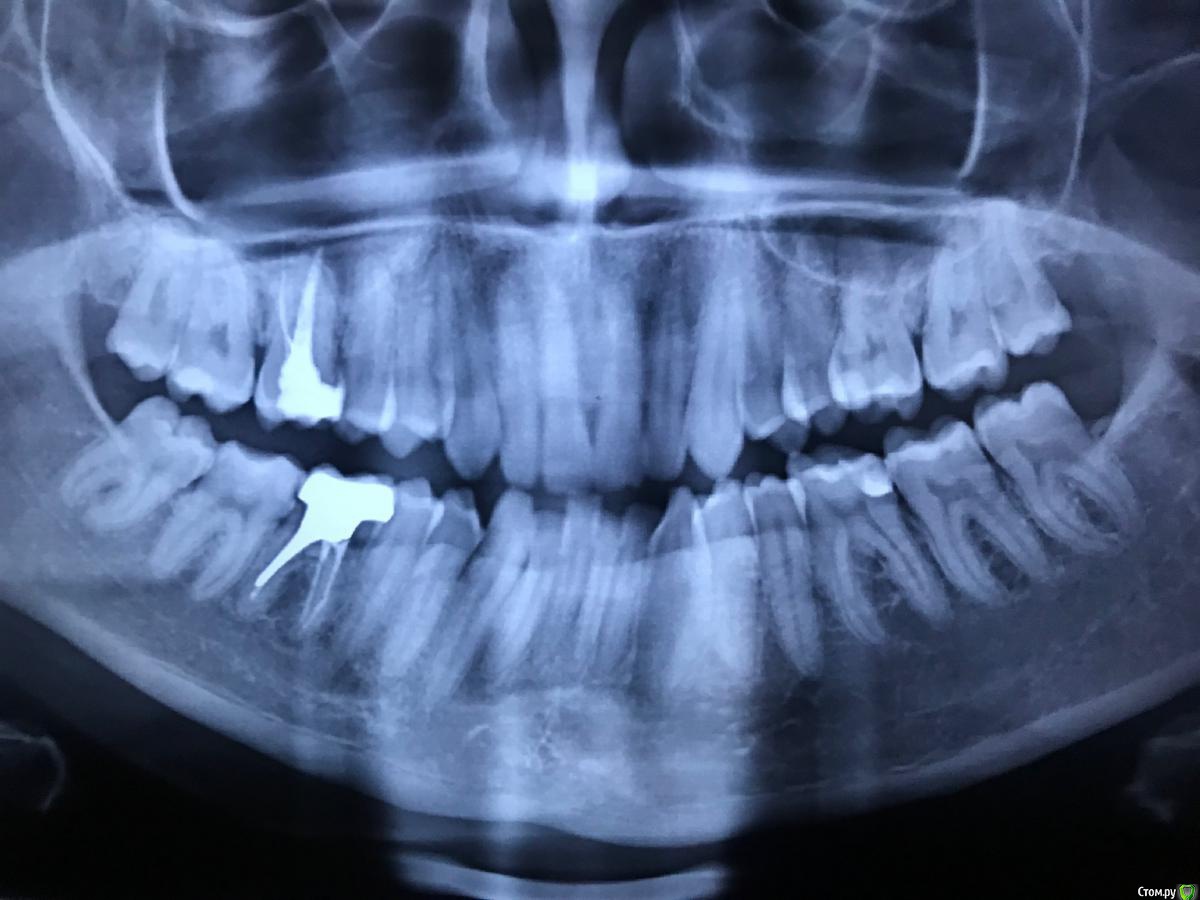

08.08 пришла на прием к стоматологу-терапевту. При осмотре полости рта (ни опухоли, ни покраснений), постукивании зубов (боли нет), ощупывании лимфоузлов (безболезненны и не увеличены) и анализе жалоб высказано предположение, что это боли от сустава. Сделана ортопантомограмма, снимок прилагаю. Заключение рентгенолога прилагаю, из найденного - 46 - апикальная гранулёма у медиального корня размером до 0,3 - 0,2 см. Но по словам стоматолога она таких болей дать не может.

09.08 проведен осмотр у стоматолога-хирурга. По снимку и по осмотру дан совет эту гранулёму пока не трогать, а за ней наблюдать. По поводу ощущений было сказано, что может быть много причин, ну да, может и сустав. Дан совет - если будет сильная пульсирующая боль и повышение температуры - пить антибиотик.